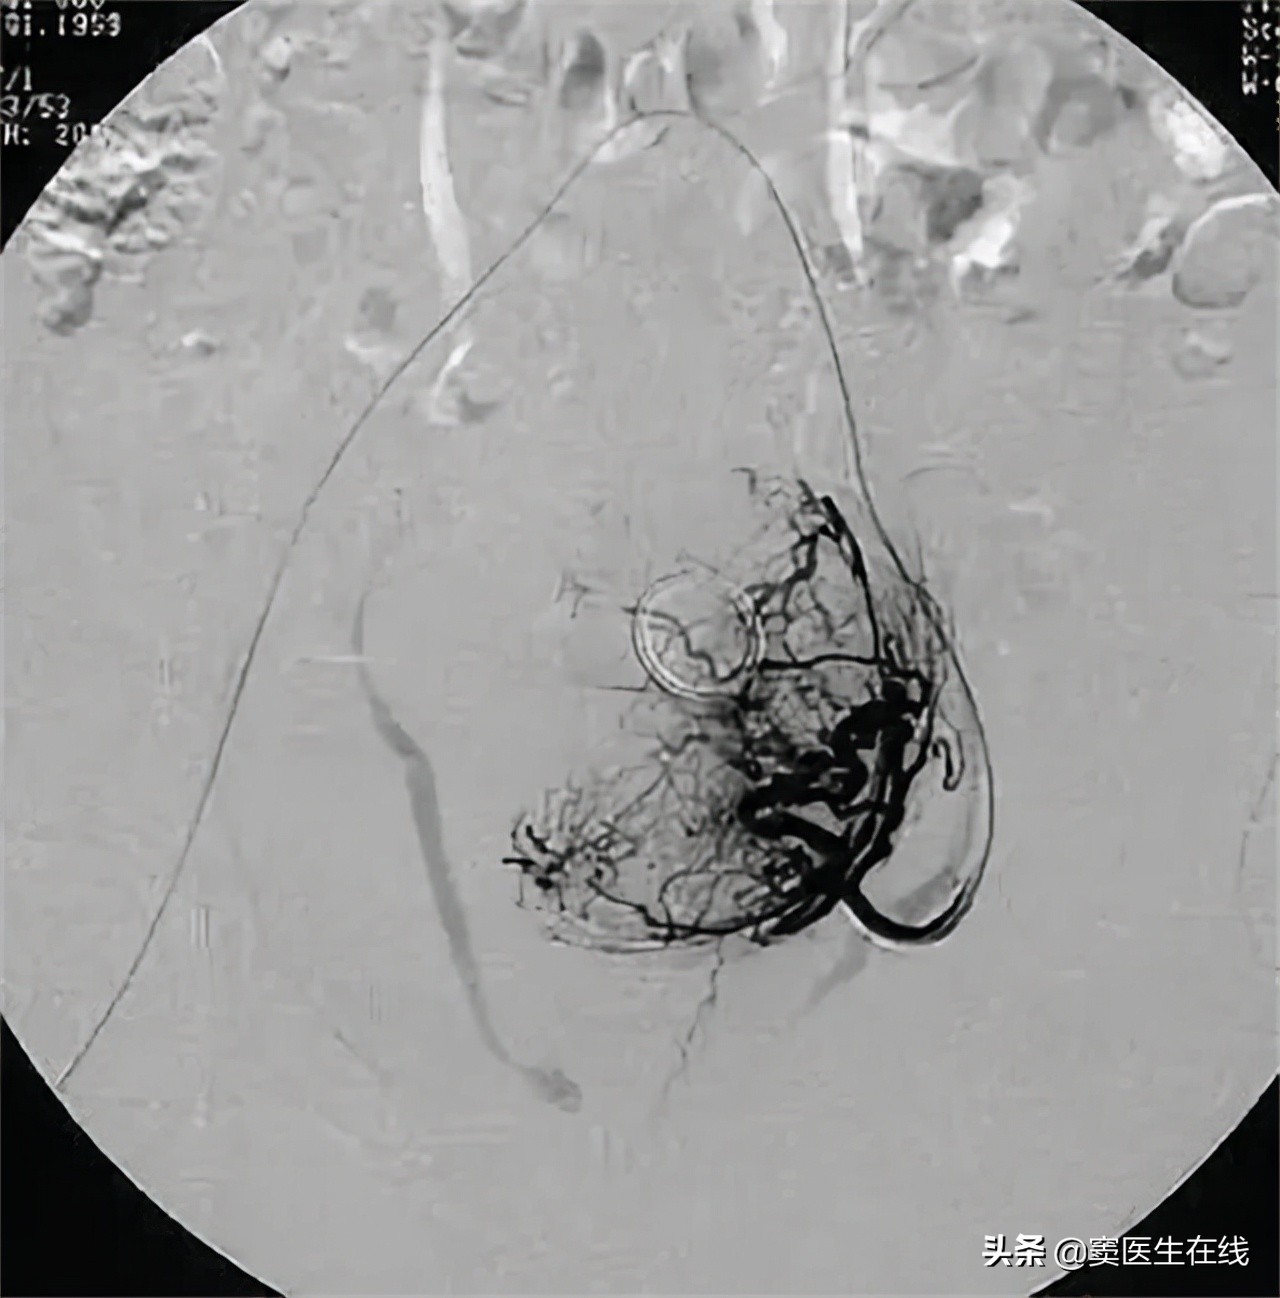

●介入治疗手术

该疗法通过影像技术,让微直径导管顺着大腿股动脉的方向,精准的进入到子宫内部动脉处,再注射造影剂,并且将病灶组织进行封闭处理,致使病灶组织缺血坏死,当萎缩到一定程度即可消除病灶。

该疗法促进在保护子宫现有组织的情况下,同时能将病灶完全清除, 术后子宫体积正常化,同时缓解了痛经、经血量异常增多等多种不适症状, 术后患者精神态势得到增强,体质也得到提升,让患者整体生活质量提到提高,是比较可行的治疗方案之一。